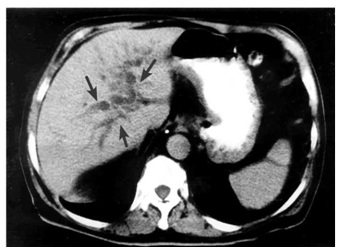

1. טומוגרפיה ממוחשבת - בדיקת הבחירה לאבחון שאתות בלבלב. בעזרתה מודגמות כיום השאת ומידת התפשטותה באחורי הצפק (רטרופריטונאום), כולל חדירה לכלי הדם הגדולים. דיוק האבחנה בטומוגרפיה ממוחשבת הוא גבוה, בלא קשר למיקום השאת (תצלום 19.9).

לעתים ייראו כיס מרה גדול על-שם קורבזיה (תצלום 20.9) והרחבה של דרכי המרה החוץ והתוך-כבדיות (תצלום 21.9).

בטומוגרפיה ממוחשבת ספירלית אפשר לראות את כלי הדם ולהבדיל בין שאת מרובת כלי דם לשאת דלת כלי דם, וכן לזהות את מיקומה וגודלה. בעזרת טומוגרפיה ממוחשבת אפשר לאתר את השאת בלבלב, ולהחדיר אליה מחט כדי לדגום אותה – FNA (תצלום 22.9).